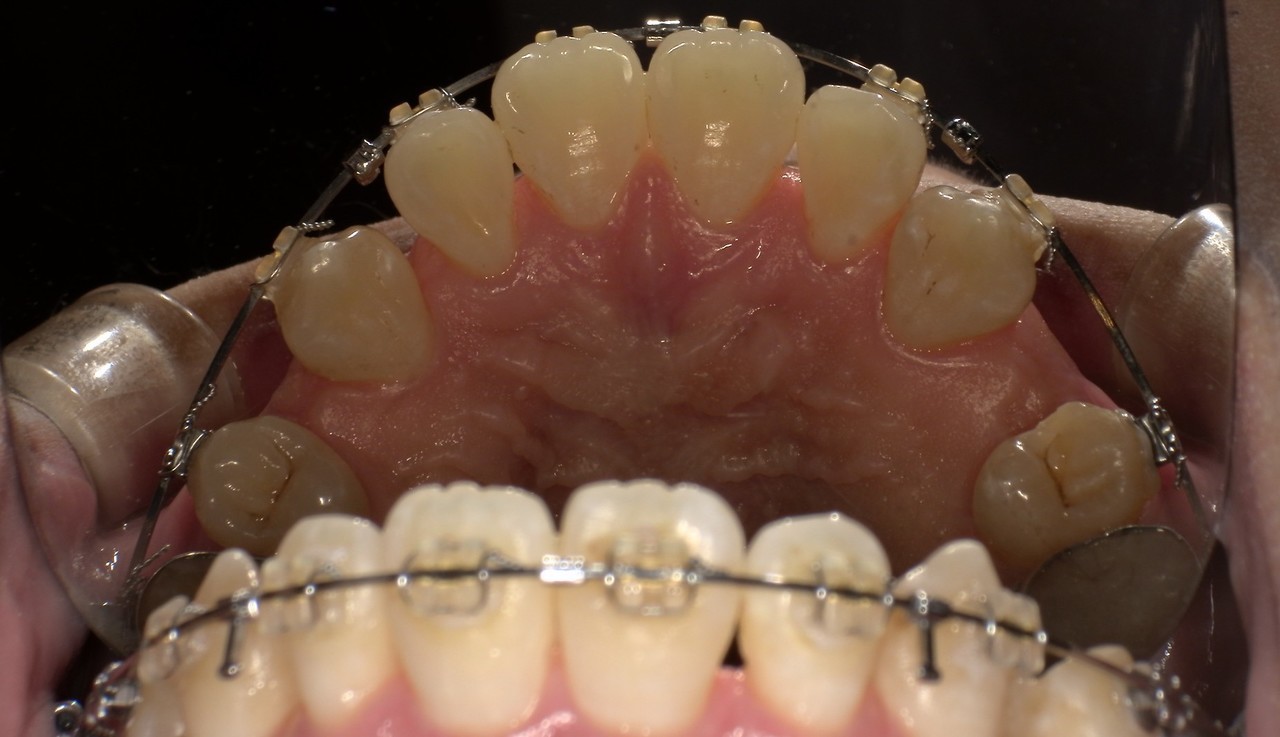

ステイン除去

BEFORE

AFTER

年齢:60代女性

治療内容:エアーフローによる歯の着色汚れ、ステイン除去

治療期間/通院回数:1回

費用: ステインコース 8,800円

リスク・副作用

①効果には個人差があり、着色汚れによっては一度に取りきれない場合があります。

施術後数時間以内に、着色効果の強いもの(コーヒー・紅茶・喫煙など)を摂取すると、歯に色素沈着が起こる可能性があります。

パウダーの刺激により歯ぐきから出血する可能性があります(痛みはほとんどありません)。